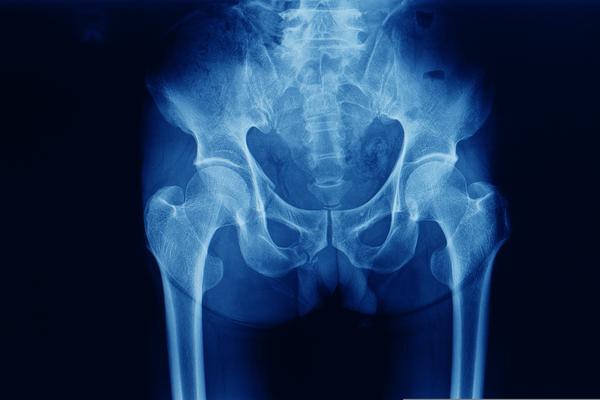

Um ensaio clínico comparou complicações mecânicas em pacientes com fraturas instáveis tratados com o uso de hastes cefalomedulares.